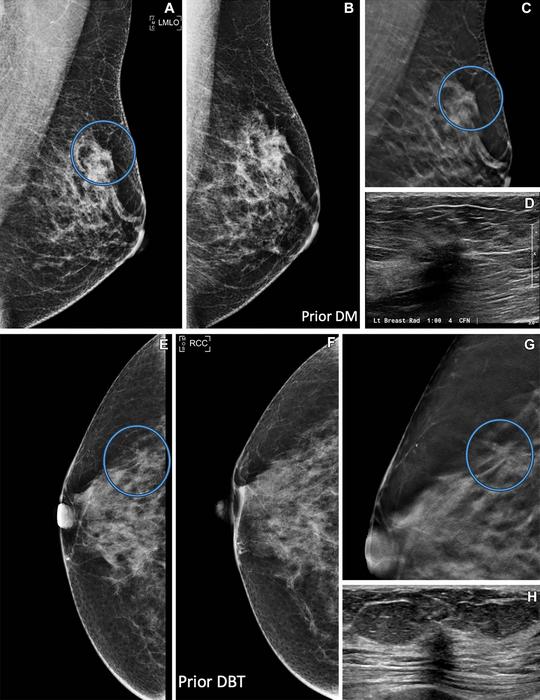

DBT is an advanced form of mammography that reconstructs pictures of the breast taken from different angles into 3D images. Studies have found that DBT has a higher cancer detection rate compared to digital mammography.

“We found that digital mammography and DBT screening mammography found the same types of cancers, but at different stages,” she said. “DBT found more aggressive cancers at an earlier stage compared to digital mammography.”

DBT had a higher cancer detection rate than mammography (5.3% versus 4.0%) and a lower rate of advanced cancers (32.7% versus 43.6%), indicating that cancers are likely being detected earlier. Cancer detection was improved when women had repeat mammograms with DBT.

Most true-positive cancer cases detected by DBT presented as masses, while fewer presented as calcifications and asymmetries.